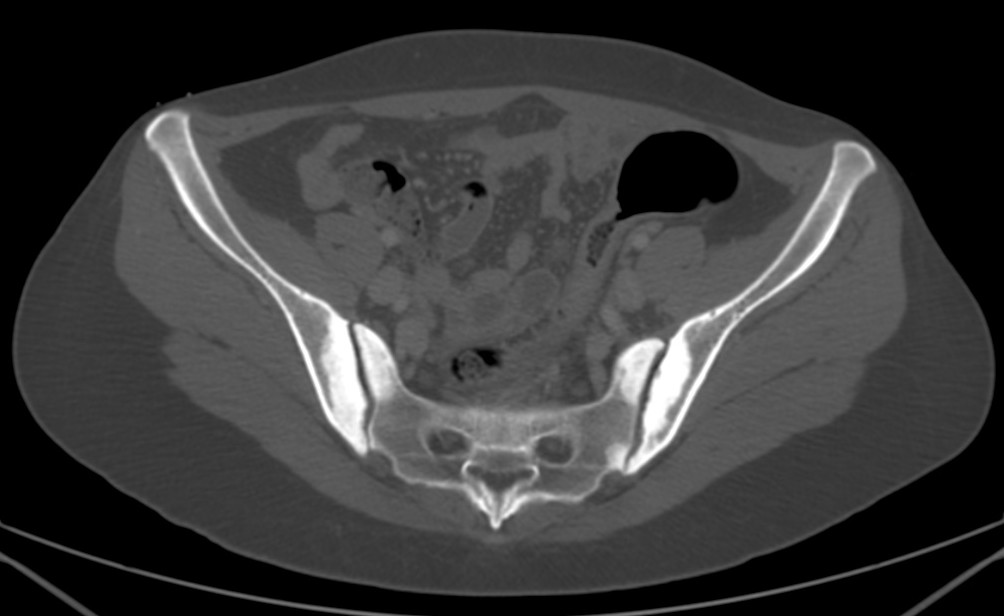

Estos hallazgos son compatibles con osteitis condensante del iliaco.

Radiologia (Placa simple y TC):

- Área triangular de esclerosis que afecta la región antero-inferior del iliaco, adyacente a la articulación sacro iliaca.

- El espacio interarticular está conservado.

- Similar área triangular de hueso reparativo en el lado sacro.